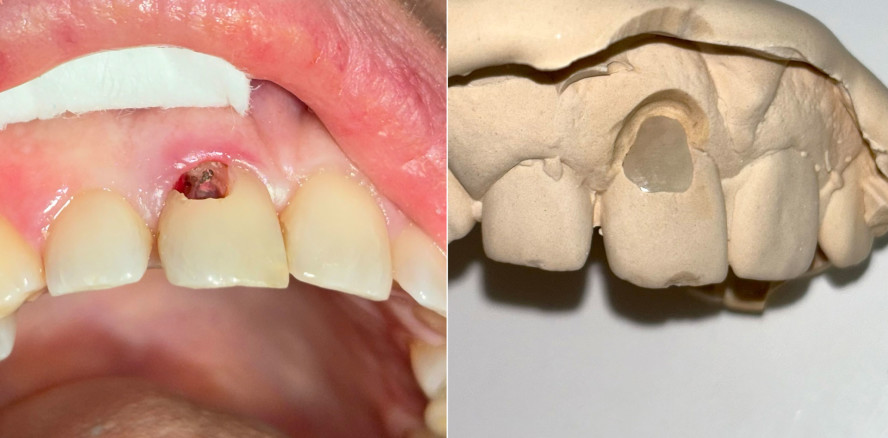

Die Behandlung erfolgte in mehreren präzisen aufeinander abgestimmten Schritten. Zunächst wurde die alte Kompositfüllung vollständig und atraumatisch entfernt, ohne eine Blutung der Schleimhaut zu provozieren. Nur durch das minimalinvasive und vorsichtige Vorgehen bei der Entfernung der insuffizienten Kompositfüllung konnte die Blutungsfreiheit erreicht und somit eine solide Grundlage für die folgenden Behandlungsschritte gewährleistet werden. Anschließend wurde die weiche Zahnhartsubstanz mithilfe eines Rosenbohrers sorgfältig exkaviert (Abb. 3). Überschüssige Guttapercha wurde ebenfalls abgetragen, um eine saubere und stabile Basis zu schaffen.

Die Sondierung ergab eine vertikale Defektausdehnung von etwa sechs Millimetern bei einer Taschensondierungstiefe von lediglich zwei Millimetern. Dies wies somit auf eine parodontale Gesundheit hin. Der gereinigte Defekt wurde anschließend mit einem lichthärtenden Flow-Komposit versiegelt, um Unebenheiten auszugleichen und die Adaptation der geplanten CEREC-­Keramikrestauration zu optimieren (Abb. 4).

Die Kavität wurde durch einen digitalen Scan abgeformt. Zusätzlich wurde eine Doppelmischabformung unter Verwendung von Alginat und Systoloid®-Hydrokolloid angefertigt, um eine spätere Anpassung der Restauration auf dem Gipsmodell durch die Zahntechnikerin zu ermöglichen (Abb. 5). Dabei spielte insbesondere der subgingivale Anteil eine entscheidende Rolle, da eine Anpassung in diesem Bereich direkt am Patienten eine erhebliche klinische Herausforderung darstellen würde. Danach wurde ein Schaumstoffpellet als temporärer Verschluss in die Kavität eingebracht, bevor ein provisorisches Onlay aus Telio® (Ivoclar) angefertigt wurde. Somit konnte eine retentive Formgebung und ein damit verbundenes Frakturrisiko bei der folgenden Entfernung des Provisoriums vermieden werden. Die Oberfläche des Provisoriums wurde bewusst rau gelassen, um eine möglichst einfache Entfernung zu gewährleisten.